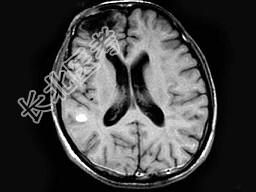

- 单项选择题男,26岁, 头痛、烦躁、意识障碍伴肢体活动障碍数天,头颅MRI检查见多发不规则小条片状结节状强化, 最可能的诊断是 ( )

A、脑结核

B、脑弓形虫病

C、化脓性脑炎

D、多发性硬化